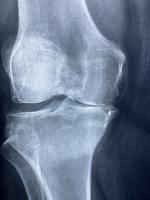

무릎통증

관절은 뼈와 뼈 사이를 부드럽게 연결하는 역할을 하며, 연골과 활액(윤활액)이 마모되면 통증과 염증이 발생하게 됩니다. 퇴행성 관절염, 류마티스, 스포츠 손상 등으로 인해 관절 보호가 필요할 때, 영양제를 통한 보조 치료는 증상 완화에 도움이 됩니다.